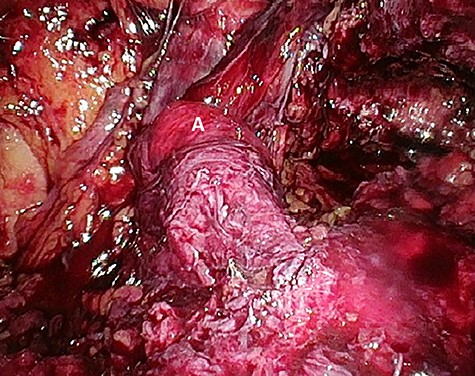

Preperitoneal view of the large hernia sac (A) ‘hidden’ in the scar tissue.

The patient agreed to proceed with diagnostic laparoscopy for a re-re-repair of the left inguinal hernia. Intraoperatively, a loop of the sigmoid colon, which previously was hidden by colonic adhesions, was fixed into a hernia orifice lateral–caudal of the preperitoneal mesh (Fig. 4). After reopening of the peritoneum and removal of the mesh, extensive preperitoneal preparation revealed the hernia orifice located in dense scar tissue not being dissected previously (Fig. 5). A new mesh (BARD® 3D Light Mesh 12 × 17 cm) was inserted and fixed medially at the Cooper’s ligament.